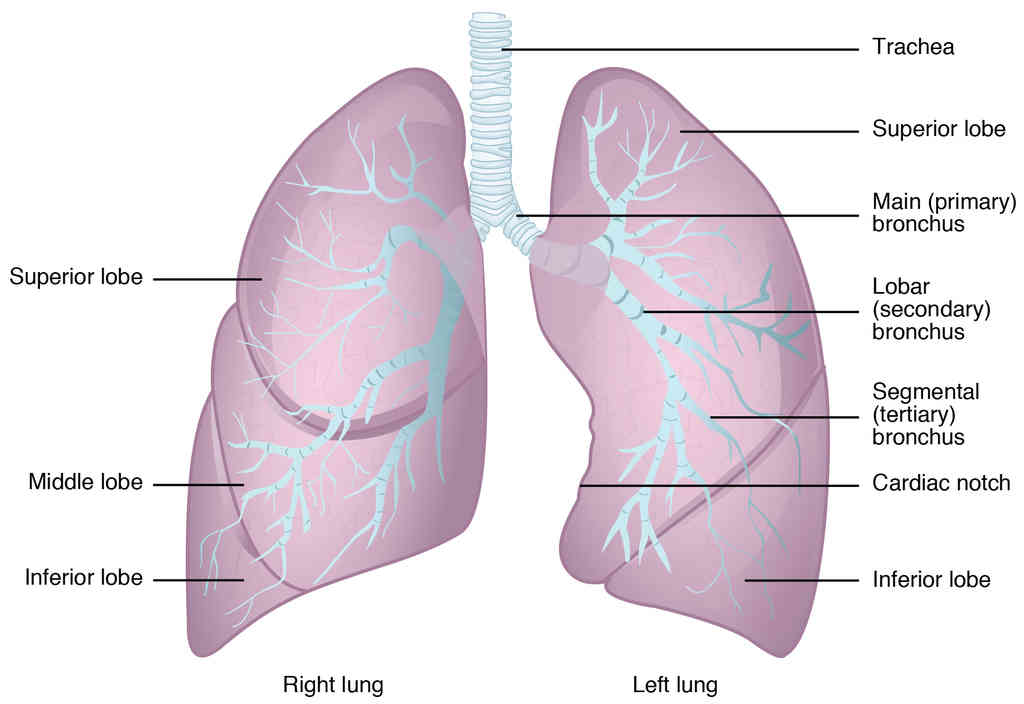

Anatomy, Physiology and Histology

This page is under construction. For now, it is just a resource of the images found in the OpenStax Anatomy and Physiology Handbook. It wil slowly change into a revision tool. Each slide has a number. Use this to refer to the slide. When completed, it will have an unlabelled section, with labelled slides in parallel. On the unlabelled slides, write your answer and use the labelled slide to assess yourself. Keep track by also noting the number on each slide. Improvement at each attempt is important, more so than full marks on a first attempt.